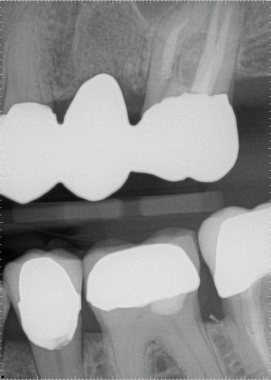

Milling this zirconia bridge took 26 minutes using the fast dry milling method provided on the CEREC MC XL Practice Lab (Fig. 3). Sintering time is reduced using this method since additional drying time after wet milling is eliminated. Sintering in the new SpeedFire furnace took another 26 minutes. Clinicians have a choice between polishing the restoration using Meisinger rubber wheels or staining and

Fig. 3

glazing the restoration. In this case, staining and glazing was performed-a cycle that took nine minutes.